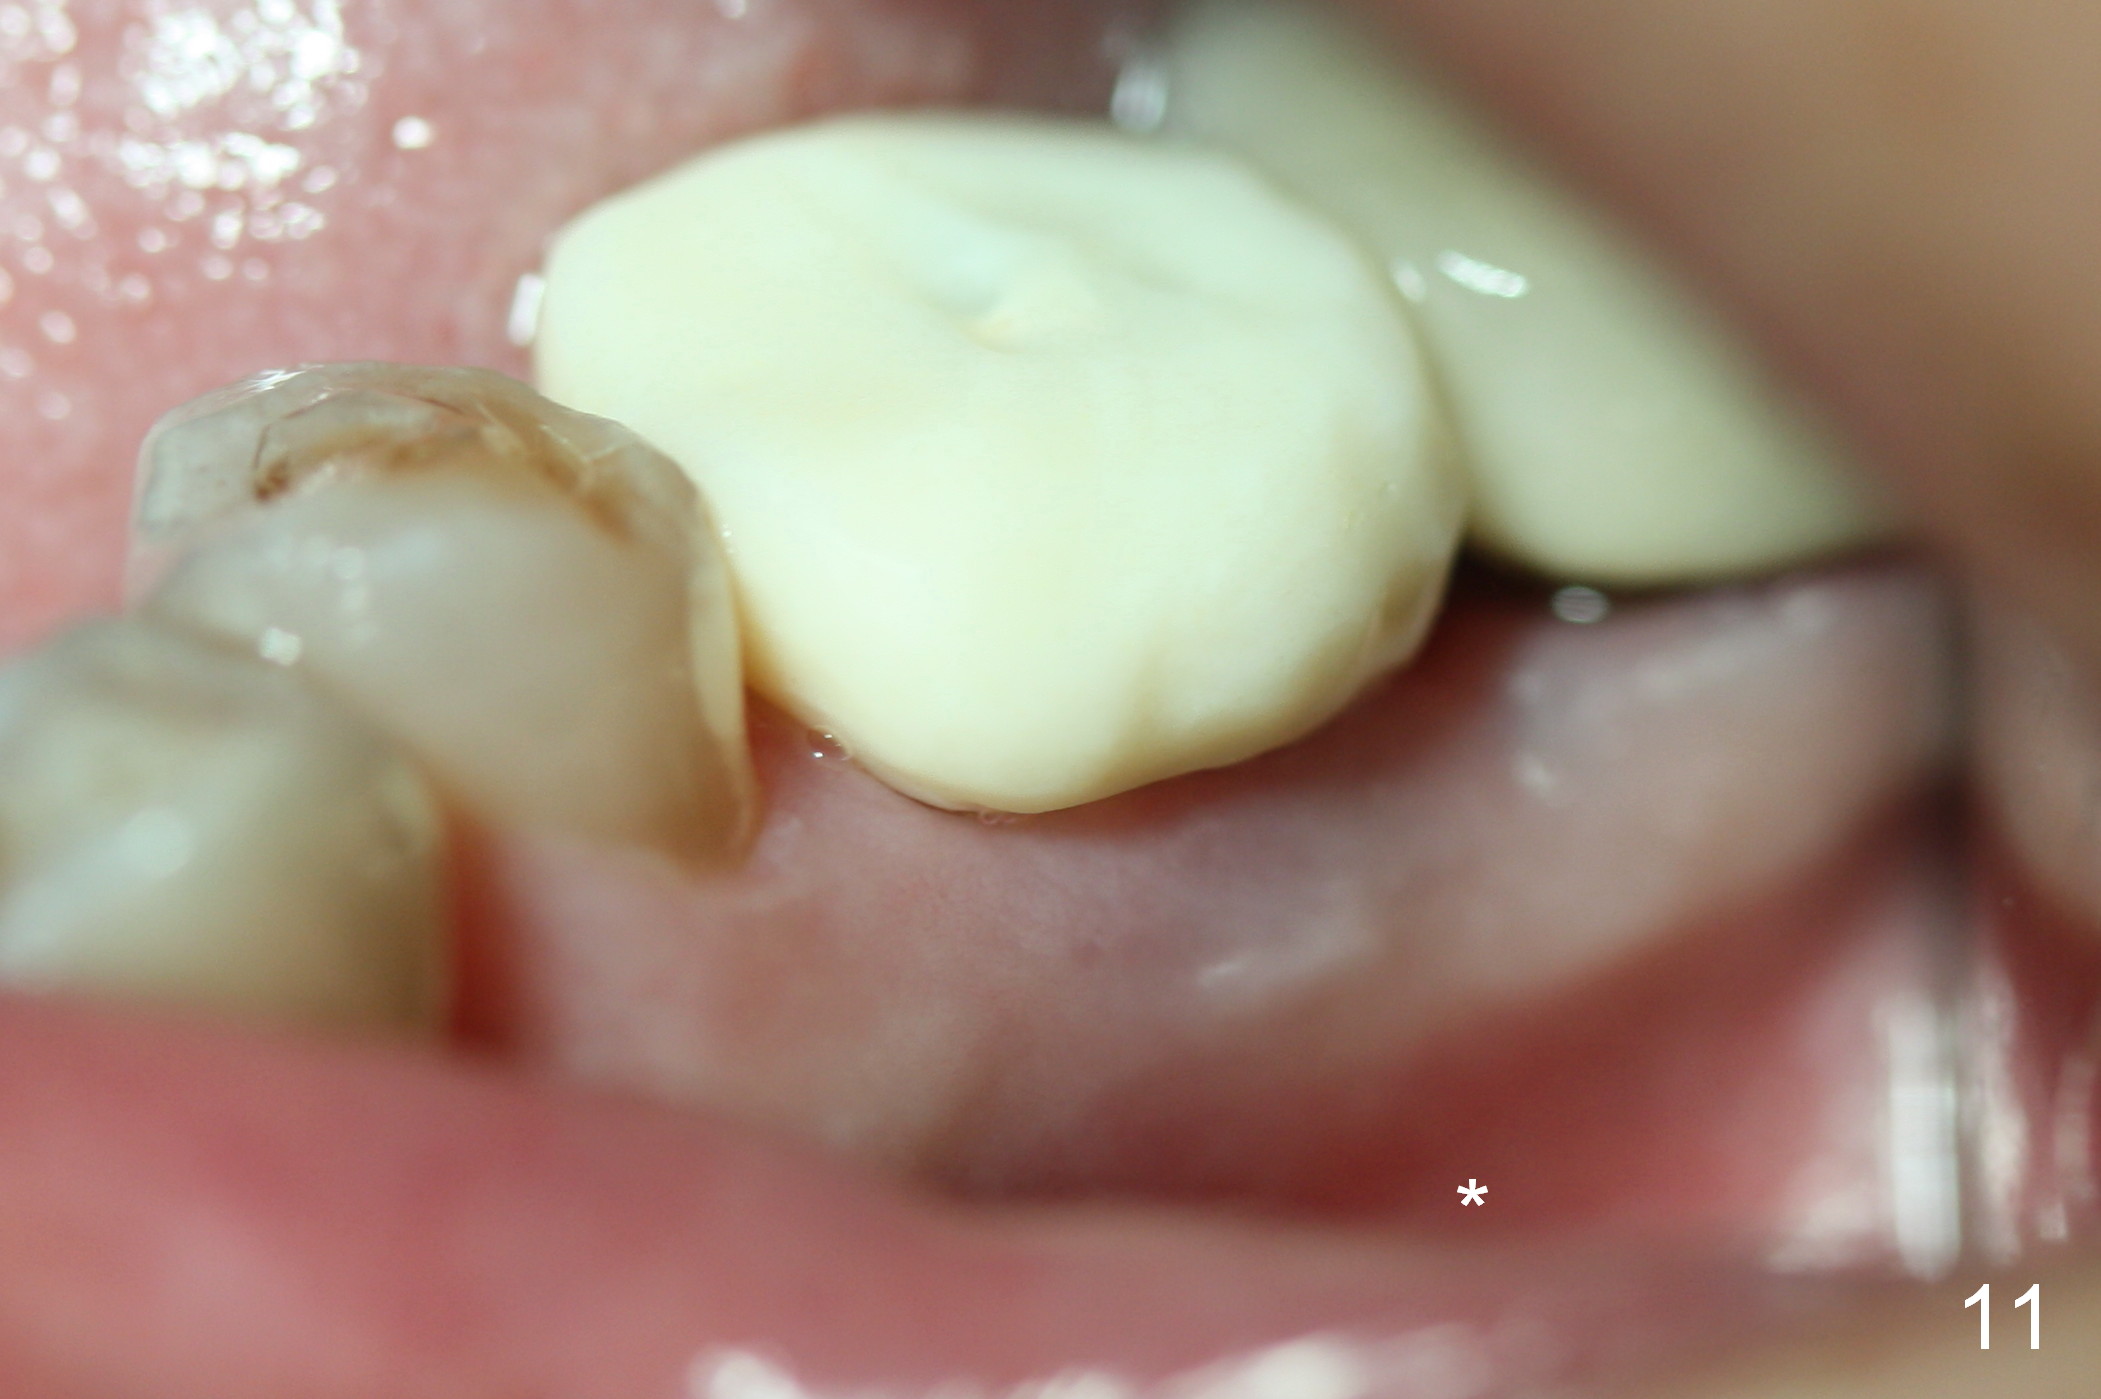

Buccal gingival swelling and mesial periapical radiolucency suggests weakened buccal plate. Osteotomy in the septum should be initiated more lingually (Fig.10e). When the osteotomy starts being deviated, correct as early as possible with a Lindamann bur and preferably over-correct (Fig.10f blue circle). The final implant placement may not encroach the buccal plate (Fig.10f red circle). Three weeks postop, the buccal infection dissolves (Fig.11). What has not disappeared is the buccal undercut (*): the basis for potential buccal perforation. Buccolingual osteotomy trajectory should be adjusted intraoperatively accordingly.

The patient returns for provisional recementation 1.5 months postop. The gingiva remains infection free (Fig.12), but the socket at the implant site has shrunk as compared to the 2nd molar site (Fig.13 arrowheads). Therefore, an implant should be placed before the socket shrinks post extraction, especially with preop lesion. Socket preservation does not prevent socket collapse. The implant is the best framework (tenting) for bone regrowth.